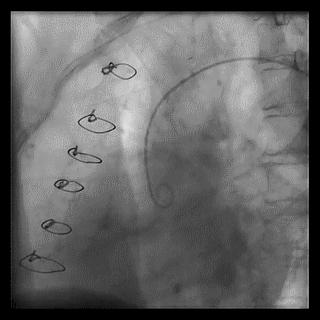

(3)冠状动脉静脉桥血管

首选导管:JR4.0;

其他导管:AL 1.0;AR 1.0

操作:升主动脉造影,寻找静脉桥血管

➢ CASE 3

AL1.0

➢ CASE 4

➢ CASE 5

升主动脉造影未见桥血管显影,原位血管造影也没发现竞争血流迹象,可以确定桥血管已闭塞,必要时可以借助冠脉CTA辅助诊断